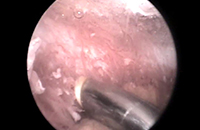

髋关节骨性关节炎(OA)以软骨退化、软骨下骨硬化和骨赘形成为特征,被认为是通过不同的病因导致相似的终末期关节退变。其中一种病因与髋关节的形态异常有关,比如髋臼发育不良。…「查看详情」